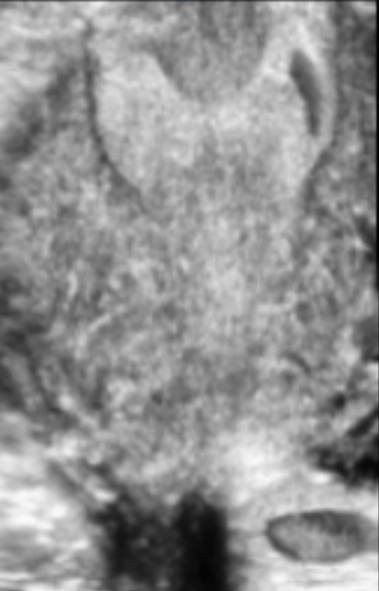

Современные экспертные УЗИ сканеры дают возможность проводить исследования всех органов в 3D. Это позволяет, используя полученный массив данных, получать диагностические сечения в любой плоскости, недоступной для обычного 2D УЗИ. Наиболее интересной является фронтальная. Например, визуализация полости матки. Диагностическая возможность выявления пороков развития превосходит все другие методы (рентгеновские и МРТ). Метод также позволяет уточнить положение ВМК (спирали) в полости матки, расположение миоматозных узлов, расположение плодного яйца на малых сроках, полипов. Сегодня современное экспертное ультразвуковое исследование невозможно без использования 3D УЗИ.